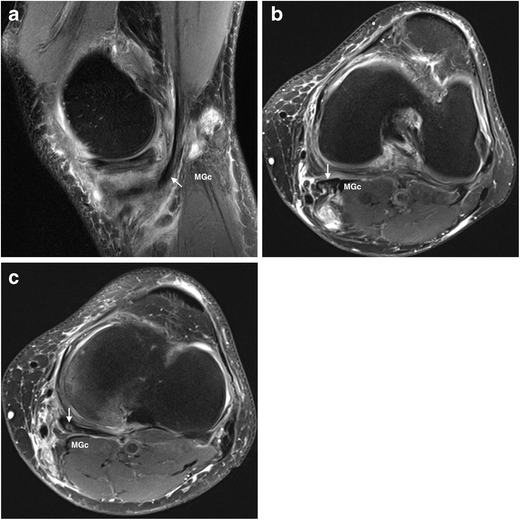

Upon rupture the characteristic rounded inferior margin of a bakers cyst becomes tapered and fluid can be demonstrated within the calf between the gastrocnemius muscle and the deep fascia. A bakers cyst is less prevalent in a paediatric orthopaedic population than in an adult population. In children it seems that a bakers cyst is seldom associated with joint fluid meniscal tear or anterior cruciate ligament tear.